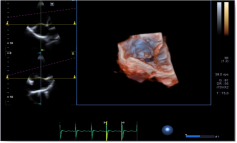

2) 心脏容积成像